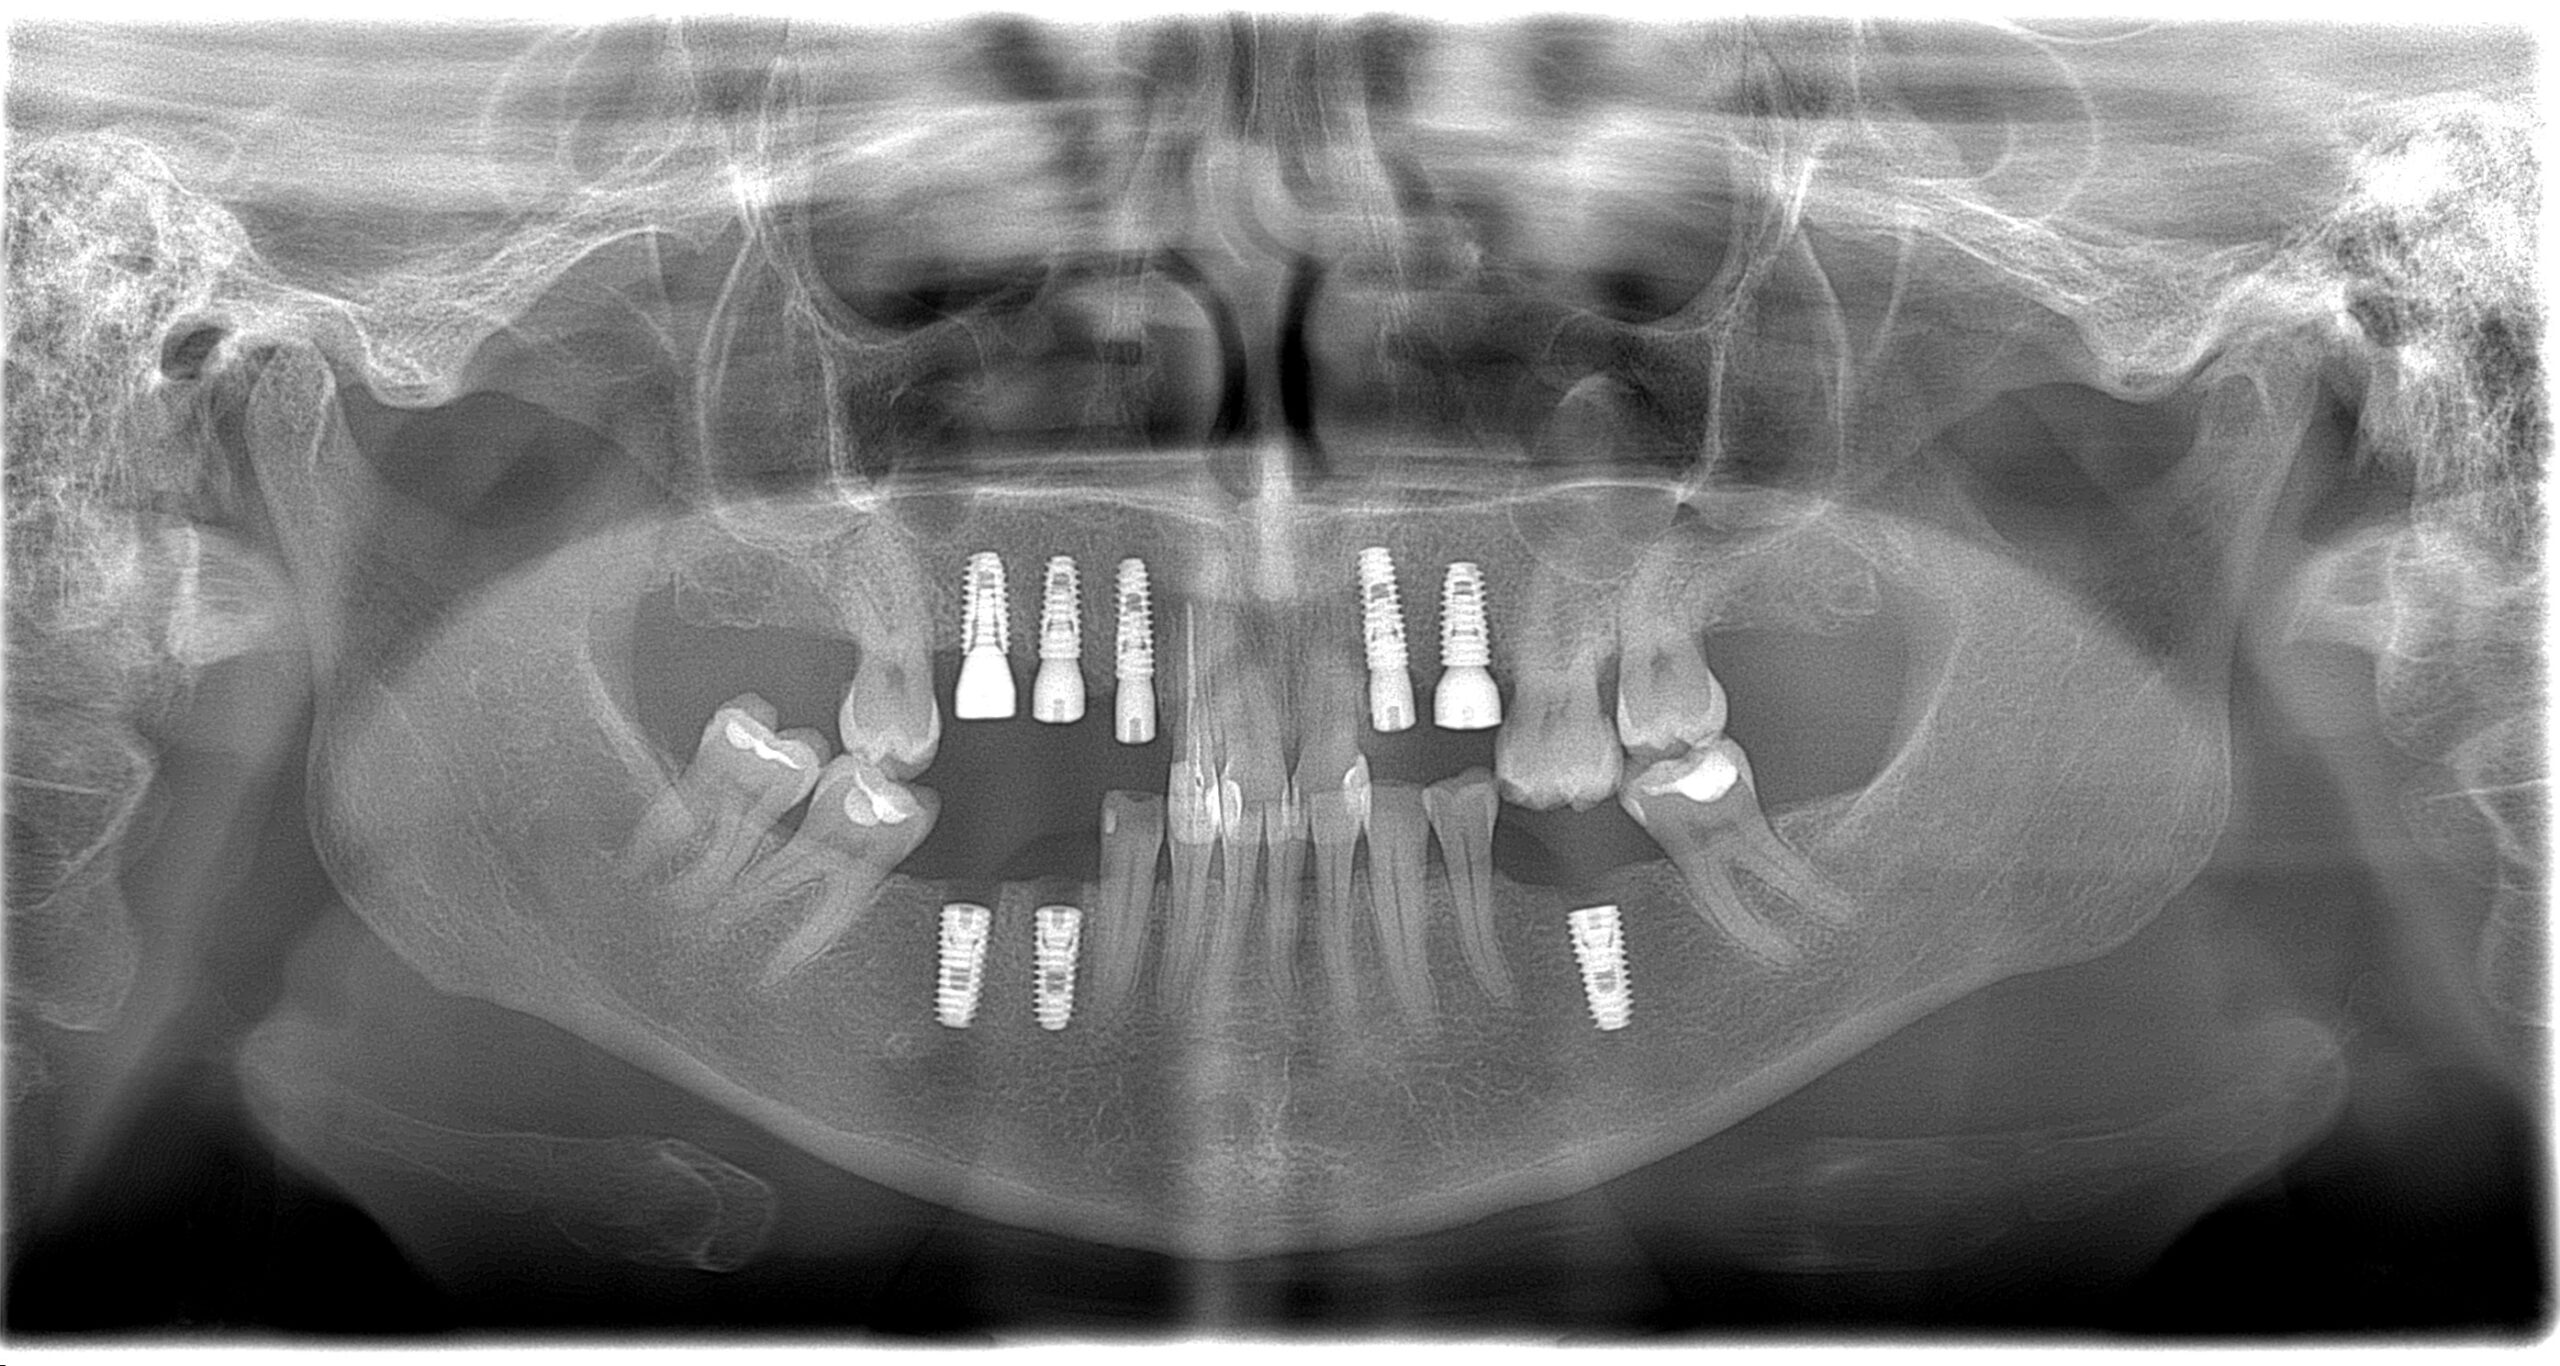

Імплантація